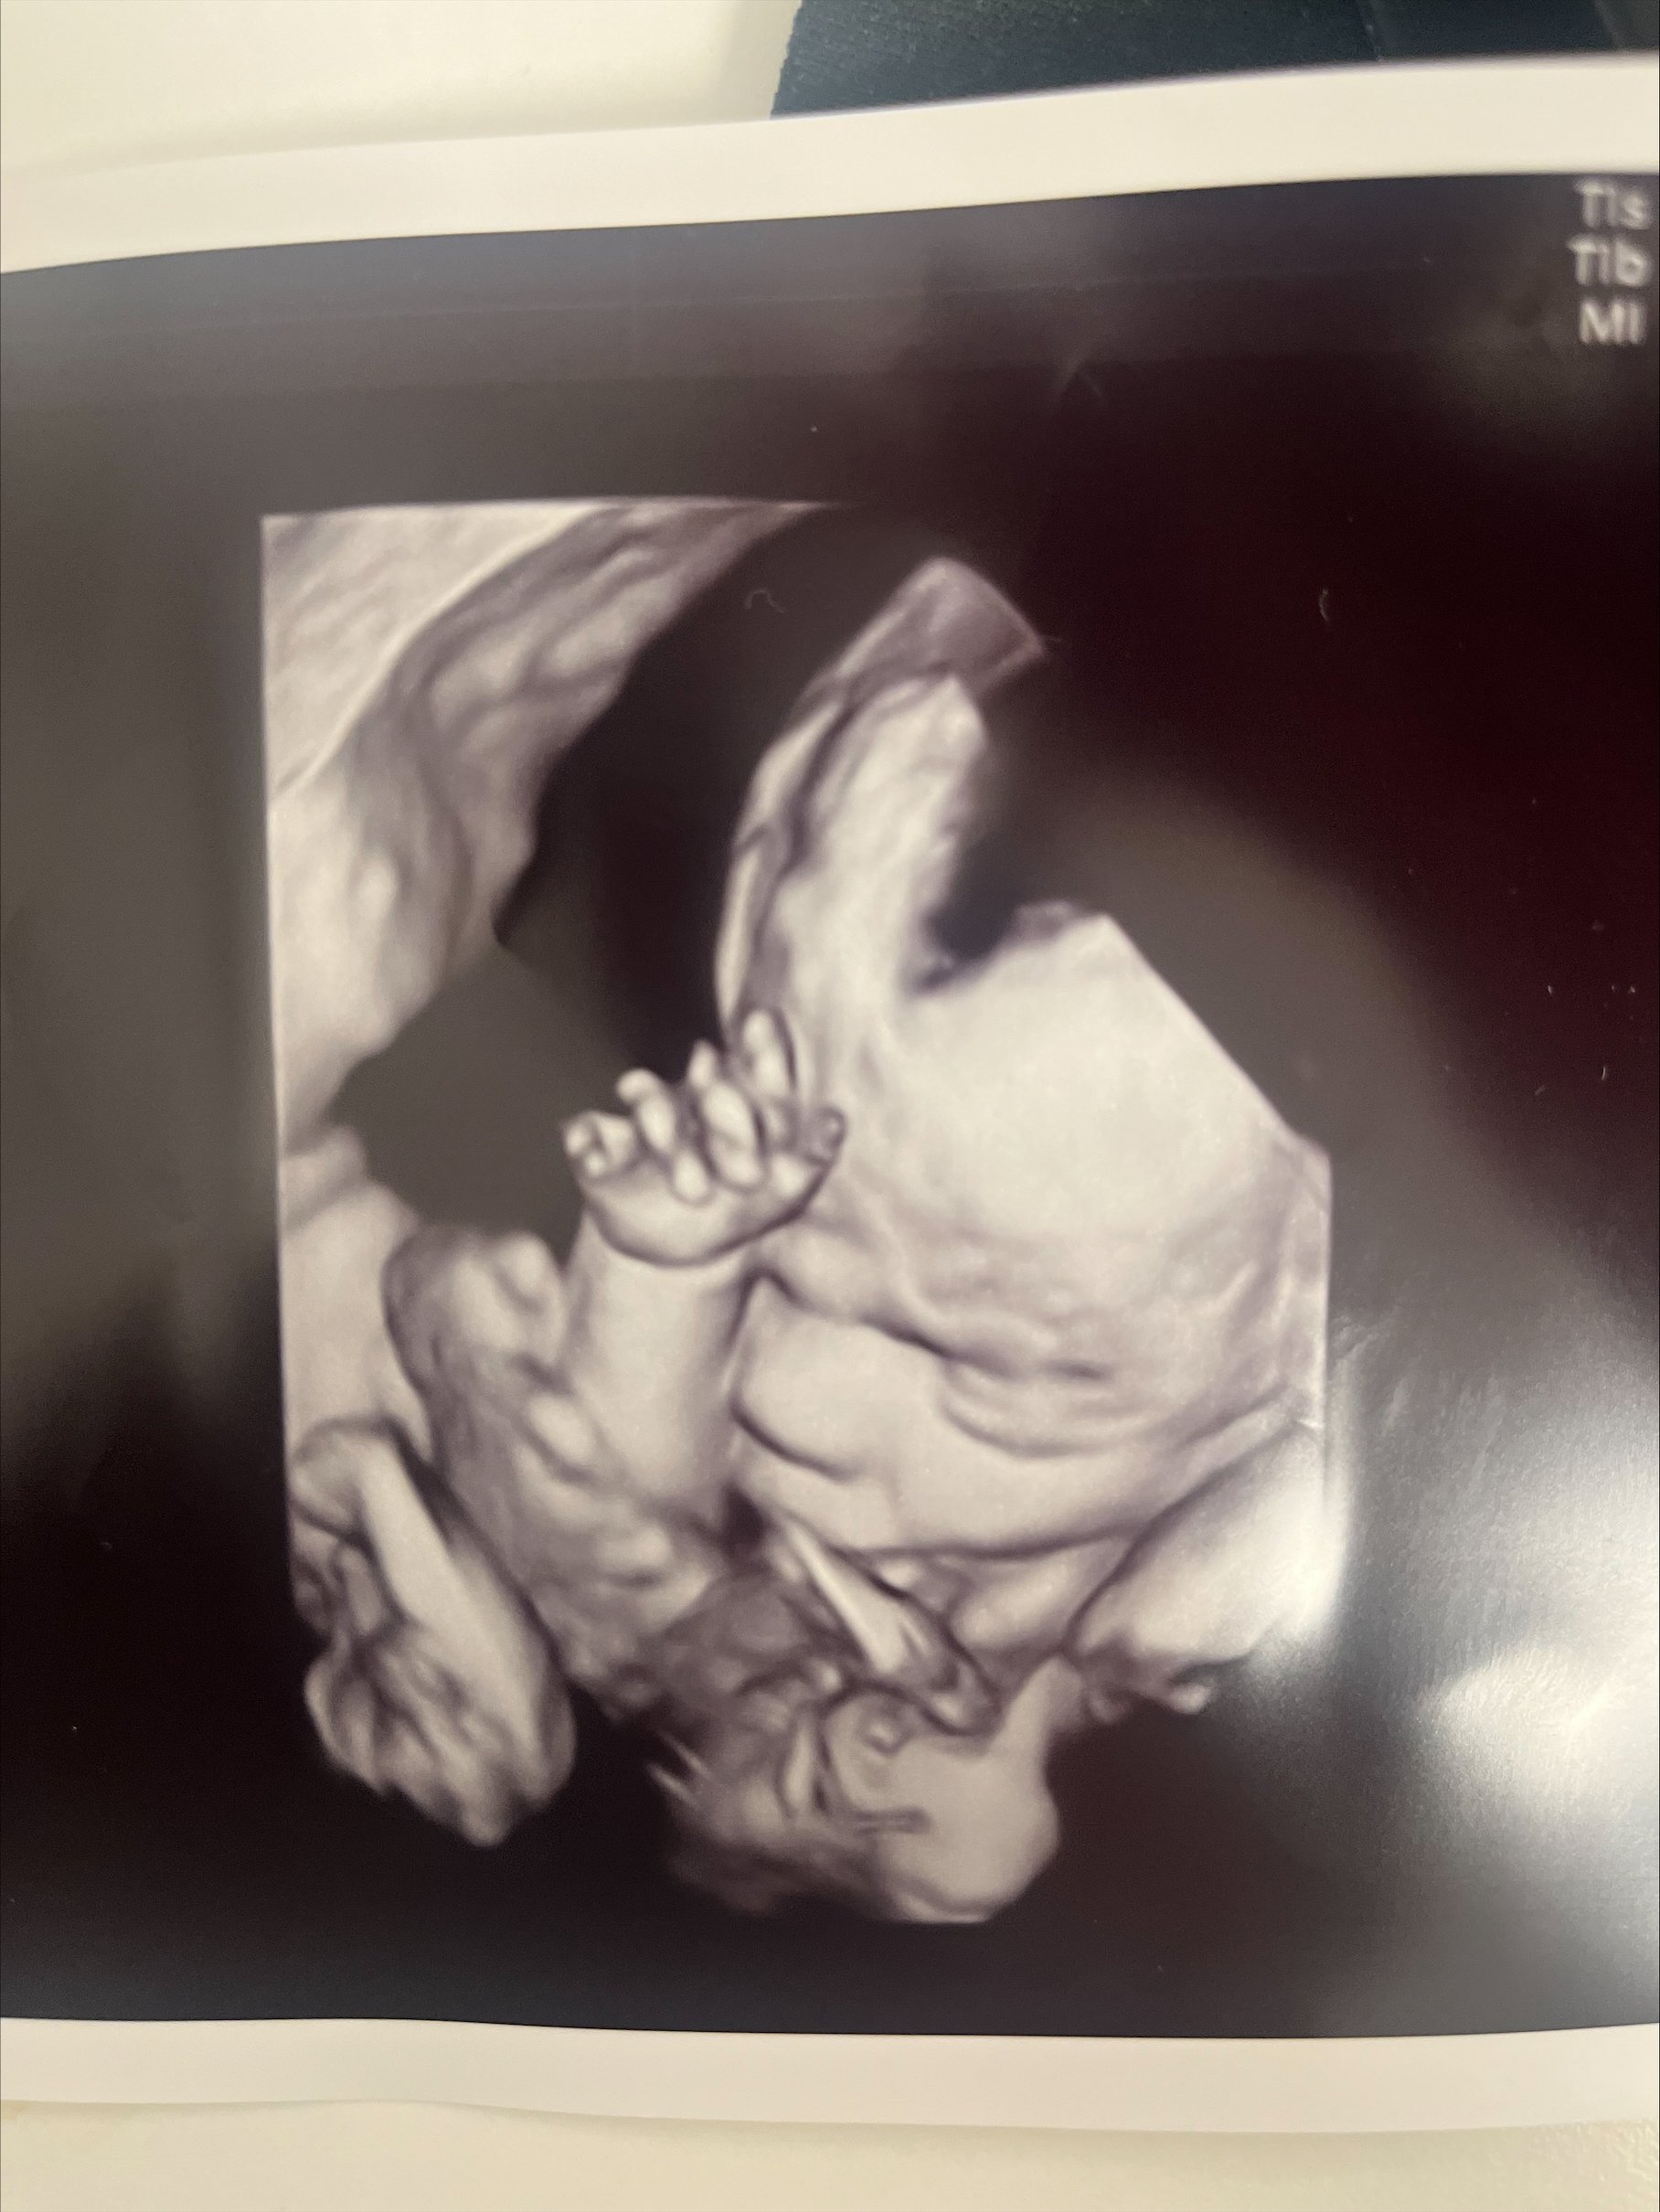

Ultralyd i 3D og 4D

Nå kan du se babyen i magen i 3D og 4D hos oss.

Ultralydjordmor

Som ultralydjordmor er det viktig for meg å holde et høyt faglig nivå. Jeg har stor forståelse for den gravide og eventuell partners ønske og behov for å få bekreftet liv, og videre ønske om å se at barnet vokser og trives inne i livmoren. For de vordende foreldrene er ultralyd det første visuelle møtet med barnet sitt, og for mange viktig i tilknytningen til barnet.

Ultralyd for gravide

Tidlig ultralyd uke 7-11 gjøres for å bekrefte liv. Vi tilbyr ultralyd fra uke 7 og gjennom hele svangerskapet.